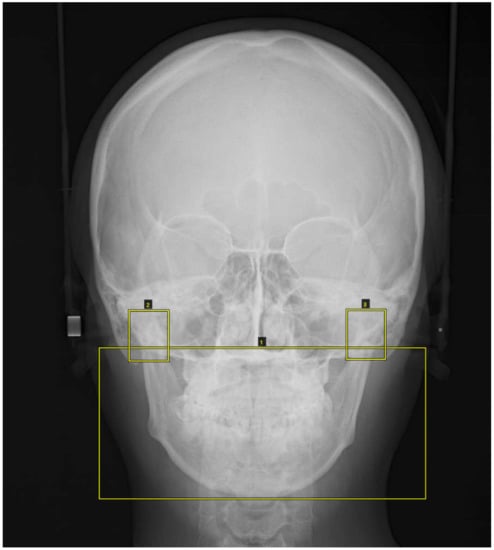

The PA cephalometric images were masked with three square markers: a lower large square containing maxilla and mandible (nasal floor and hard palate region~inferior border of mandible) plus right and left small squares containing the condylar process (Figure 1).

Figure 1.

The posterior–anterior (PA) cephalometric images were masked with three square markers: a lower large square containing maxilla and mandible (nasal floor and hard palate region ~ inferior border of mandible) plus right and left small squares containing the condylar process.